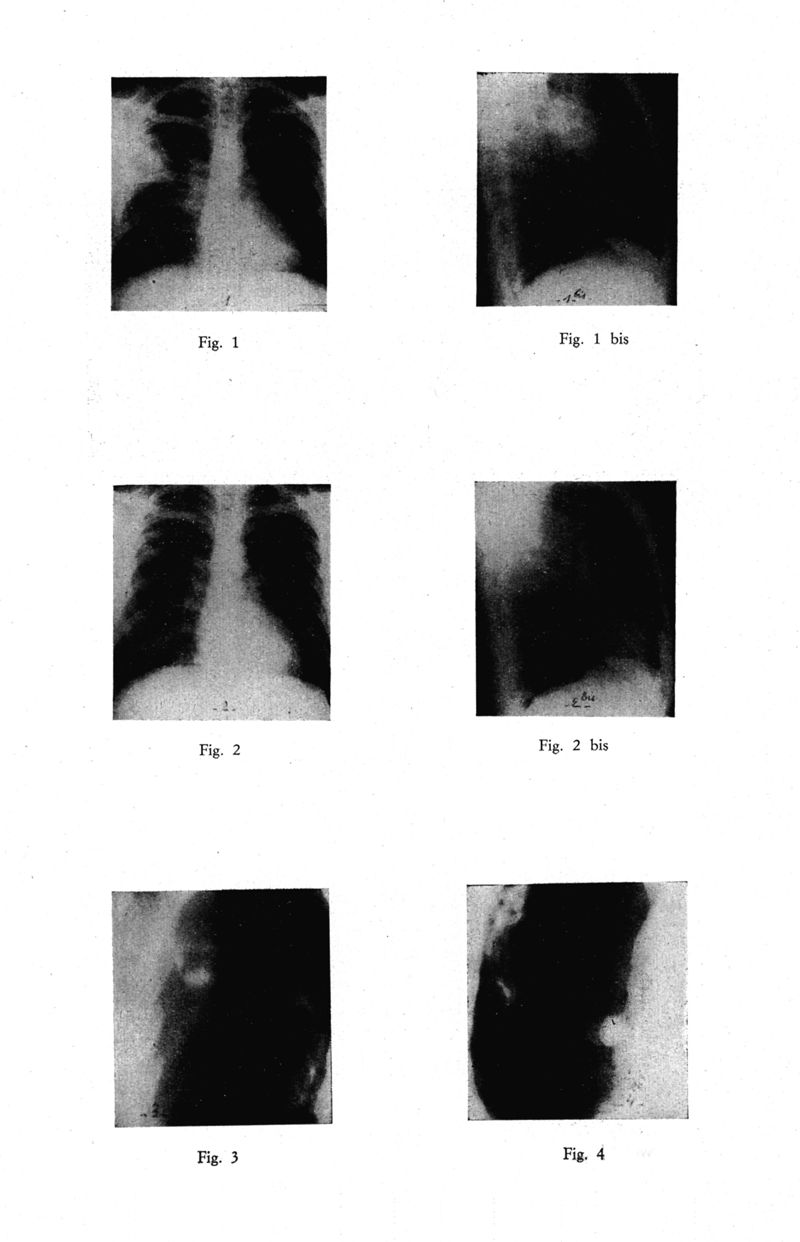

Médecine tropicale : Revue du service de santé des troupes de marine

. - Marseille : Ecole d'application du service de santé des troupes de marine, 1964.